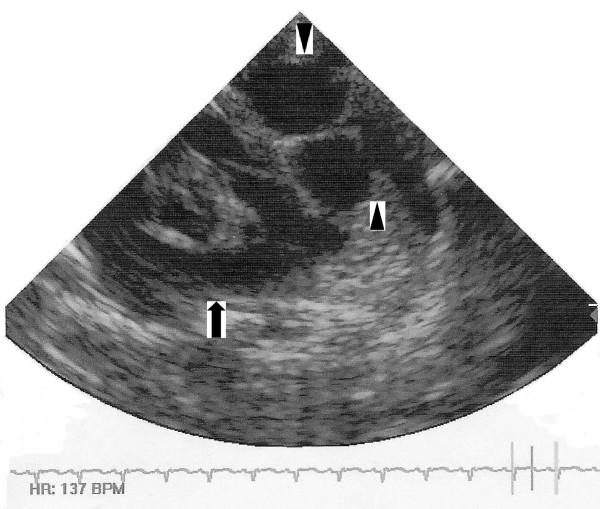

We report one such case that was mistaken for other entities in both the prenatal and immediate post-natal period. Initial and follow-up antenatal ultrasound scans demonstrated a multicystic lesion in the left chest, and the mother was counselled about the possibility of her baby having a congenital diaphragmatic hernia. Initial post-natal chest radiographs were reported as normal. An echocardiogram and thoracic computed tomography scan confirmed a complex multiloculated cystic mediastinal mass. The working diagnoses were of a mediastinal teratoma or congenital cystic adenomatous malformation. At operation, the lesion was compressed by the left lung and was found to be close to the left phrenic nerve, which was carefully identified and preserved. After excision, histopathological examination of the mass confirmed the diagnosis of cystic hygroma. Postoperative dyspnoea was observed secondary to paradoxical movement of the left hemidiaphragm and probable left phrenic neuropraxia. This settled conservatively with excellent recovery.

我们报告了这样一例在产前及产后即刻均被误诊为其他疾病的病例。初次及后续产前超声检查显示左胸有一多房性病变,医生告知母亲其婴儿可能患有先天性膈疝。产后初次胸部X线片报告正常。超声心动图和胸部计算机断层扫描证实为复杂的多房性纵隔囊性肿块。初步诊断为纵隔畸胎瘤或先天性囊性腺瘤样畸形。手术中,病变被左肺压迫,发现其靠近左膈神经,遂小心识别并予以保留。切除后,肿块的组织病理学检查确诊为囊状水瘤。术后观察到因左半膈矛盾运动及可能的左膈神经失用导致呼吸困难。经保守治疗后症状缓解,恢复良好。